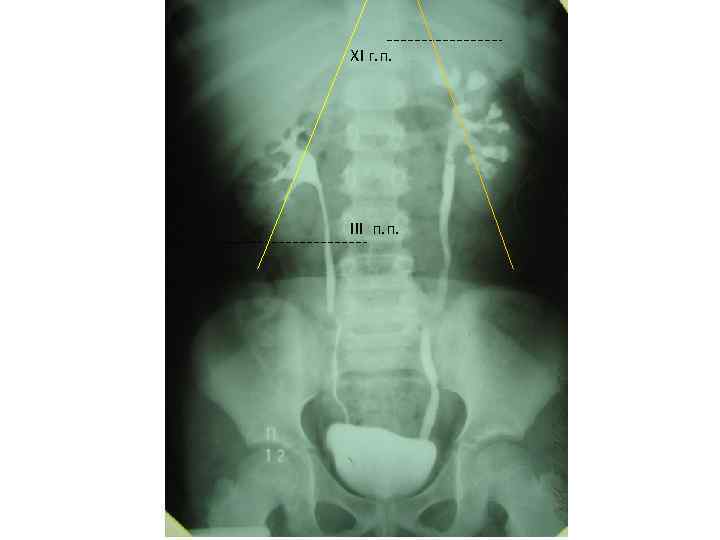

XI г. п. III п. п.

Показания и противопоказания к проведения экскреторной урографии – Показания: • Наличие обструктивных уропатий или подозрение на них • Травматические повреждения почек • Аномалии количества и взаиморасположения почек или подозрение на данную патологию • Боли в животе, энурез, артериальная гипертонией у детей, имеющих наружные урогенитальные аномалии • Наличии опухолей в животе • Рецидивирующие инфекции мочевых путей – Противопоказания • Возраст ребенка менее 2 нед. Из-за низкой концентрационной способности почек • Систолическое артериальное давление ниже 70 мм. рт. ст. • Почечная недостаточность • Аллергические реакции на контрастные препараты • Удельный вес мочи ниже 1010.

Экскреторная урография